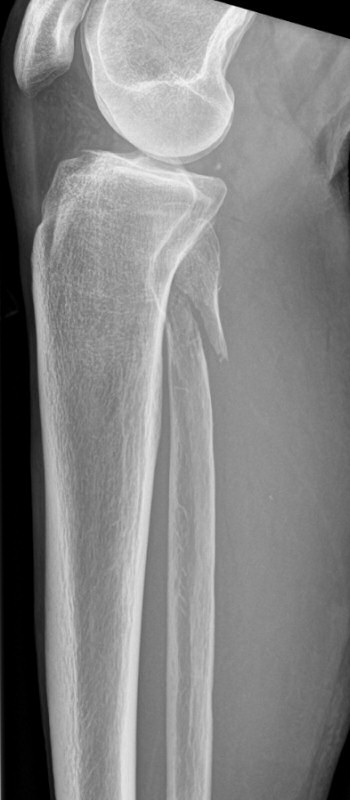

Maisonneuvefraktur

Proximal fibulafraktur (AO C3), ruptur av membrana interossea ned till fotleden och fraktur i mediala malleolen eller ruptur av lig. deltoideum.

Exempel på maisonneuvefraktur. Proximal spiralformad fibulafraktur, var svullen och ömmande runt båda malleolerna men ingen fraktur distalt.